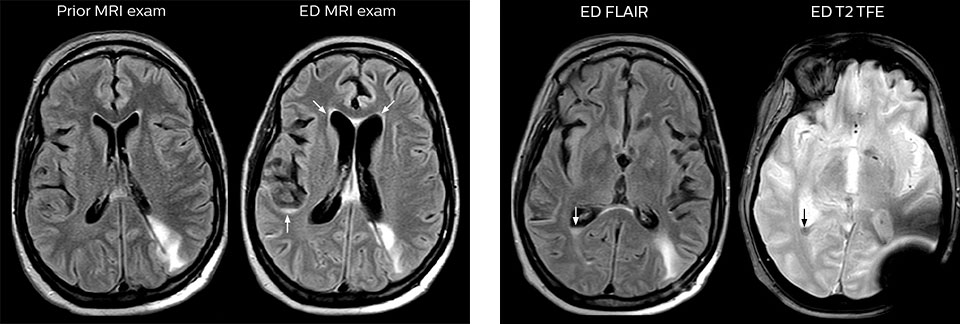

“We use mDIXON TSE extensively in our spine imaging in the emergency room,” says Dr. Karis. “It’s particularly nice in that it is very robust with regard to susceptibility type of problems that would come up with traditional spectral fat-saturated images; these problems are essentially eliminated with the mDIXON technique. In our ED environment it’s really nice to have the fat-free imaging that goes along with the mDIXON technique.

“For the thoracic and cervical spine routine non-contrast exam, for example, we perform one mDIXON T2 TSE sequence, which provides us with two outputs: the fat-and-water-together T2-weighted images, as well as the water-only sagittal T2-weighted images. And then we also perform an axial gradient echo exam.”

cervical spine mri in ed

Cervical spine routine exam

This patient presented with headache that was worse with neck flexion and we see a Chiari 1 malformation with low-lying cerebellar tonsils as well as some degenerative cervical thrombolytic change.